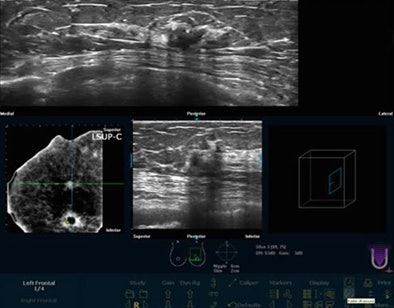

To test the CAD algorithm, Chang and colleagues examined its performance on 45 breast ultrasound cases acquired with U-Systems' SomoVu scanner. The system scans the entire breast with a 14.5-cm probe containing 768 elements, providing a minimum slice thickness of 0.2 mm. However, slice spacing is generally set at 0.6 mm to reduce image file sizes, Chang said.

Resolution in A view (y-axis) is 76 pixels/cm, resolution in B view (x-axis) is 35 pixels/cm, and resolution in C view (z-axis) is 16 pixels/cm. C view represents a computer reconstruction of the images, so resolution is lower than in A view.

| Image data are acquired on the SomoVu ScanStation in three planes at different resolutions within the scan space. Resolution in A view (y-axis) is 76 pixels/cm. Resolution in B view (x-axis) is 35 pixels/cm. Resolution in C view (z-axis) is 16 pixels/cm. C view represents a computer reconstruction of the images, so resolution is lower than in A view. Below, whole-breast scan before application of CAD. All images courtesy of Ruey-Feng Chang, Ph.D. |